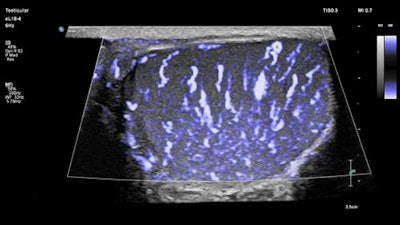

- The eL18-4 PureWave linear-array transducer provides detailed resolution through fine-elevation focusing.

- MicroFlow Imaging enables assessment of blood flow in small vessels.

The eL18-4 ultrasound transducer is designed for small-parts imaging. Image courtesy of Philips.The new package bolsters clinicians' capacity to evaluate and treat small parts through an easy-to-perform exam, according to Vitor Rocha, business leader of the ultrasound group at Philips.